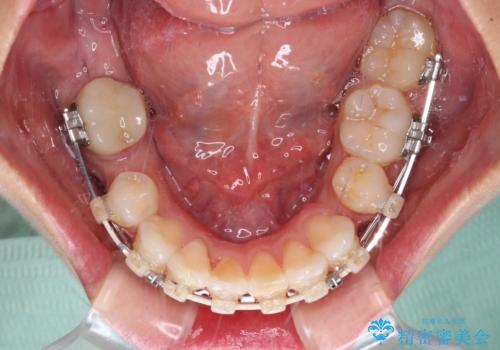

埋伏している右下第二大臼歯は、牽引して咬合に参加させることで計画しましたが、癒着などにより移動困難な場合には、抜歯の上インプラント補綴治療を行うこととしました。

右下の埋伏歯はやはり癒着しており、抜歯の後にインプラントを埋入することとなりました。

埋伏歯の牽引や、奥歯の咬み合わせ改善、インプラント補綴治療と治療期間が延びてしまう要素が多く、治療は難航しましたが、最終的に非常に満足のいく仕上がりとなりました。